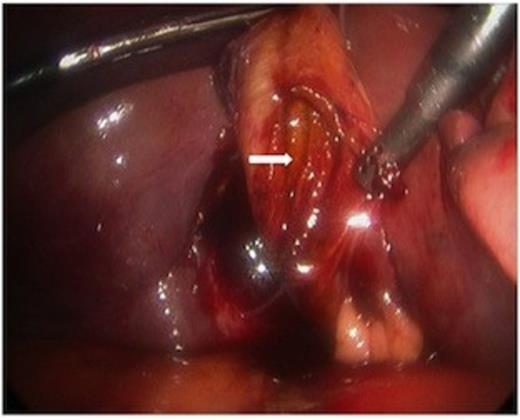

While hepatic contrast extravasation in a stable patient is typically treated with angioembolization, proximity to the gallbladder was concerning for gallbladder injury. Exploratory laparoscopy was performed and the gallbladder was found to be perforated and nearly completely avulsed from the liver (Figures 2 and 3).

The body of the gallbladder was perforated on its inferior surface (arrow).